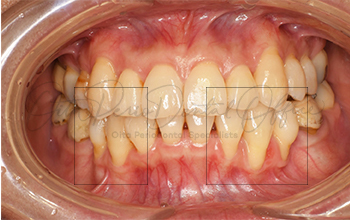

| 治療期間 | 6週間 |

|---|---|

| 治療費 | 13万 |

| 治療内容 | 右下1・左下1根面被覆(結合組織移植術) |

| 治療のリスク | ドナーサイトが必要、術後の疼痛・腫脹、術後の注意事項をフォローしない場合は失敗の 可能性あり |